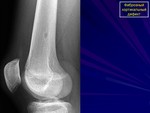

На рентгенологическом снимке обнаруживаются светлые очаги с четко очерченными границами склерозированной ткани, также наблюдается вздутие кортикального слоя. В случае неоссифицирующей фибромы в патологический процесс включен костномозговой канал.

3. Рентгенологическая картина при МФДК весьма характерна и почти всегда позволяет поставить правильный диагноз. Краевой дефект костной ткани расположенный эксцентрически в метафизарных отделах трубчатых костей, никогда не переходит через ростковую зону, имеет ровный или полициклический контур в виде тонкой полоски склероза, отделяющий очаг от совершенно неизмененной окружающей кости и при динамическом наблюдении смещающийся в сторону диафиза.

Рентгенологически очаг просветления с чёткими склерозированными границами; вздутие кортикального слоя.